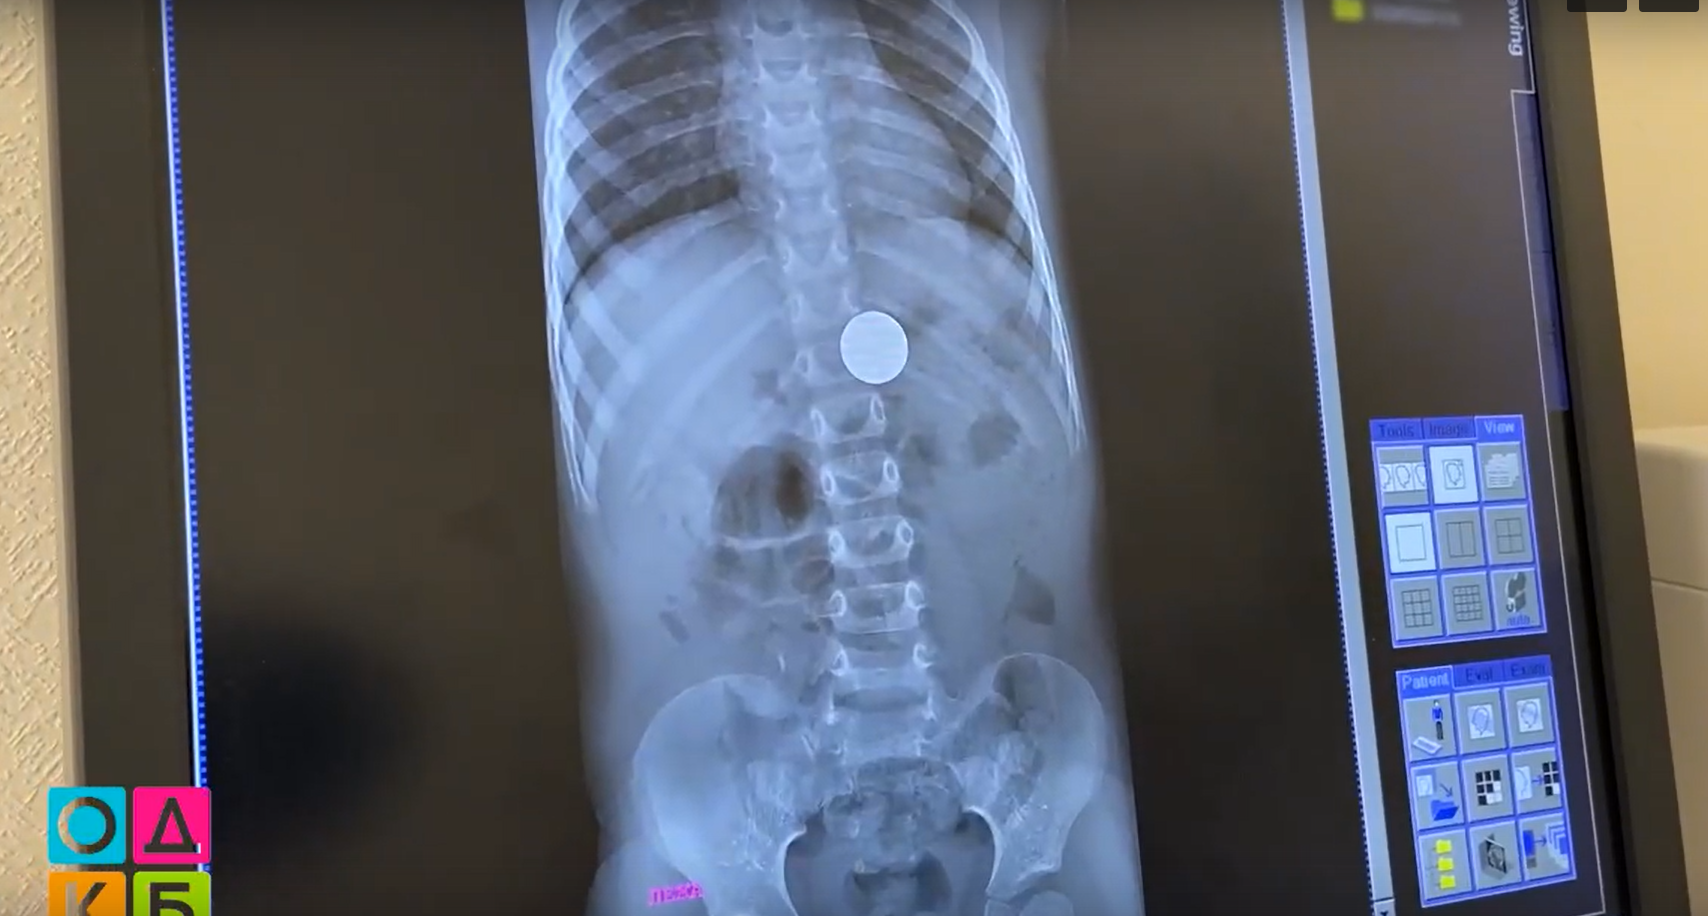

Ребенок проглотил рублевую монету

Ребенок проглотил рублевую монету 107 фото